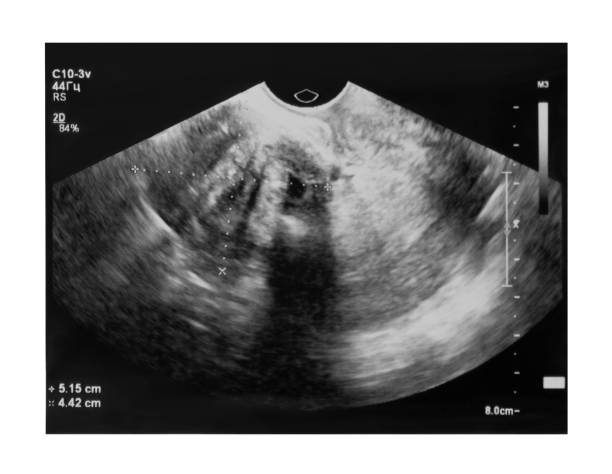

자궁근종은 자궁 내부나 외부에 발생하는 양성 종양으로, 자궁근육 내부에서 발생하는 경우가 가장 많습니다. 자궁근종은 여성들의 월경기에 더욱 빈번하게 발생하며, 대부분의 경우는 악성 종양으로 전이되지 않습니다.

자궁근종은 대개 증상이 없어서 여성들이 모르고 지나칠 수 있습니다. 그러나 종양이 커지거나 수가 많아지면 자궁근육을 압박하거나 옆에 있는 장기를 압박할 수 있습니다. 이러한 압박은 복통, 가끔 출혈, 배뇨 불편 등의 증상을 일으킬 수 있습니다.